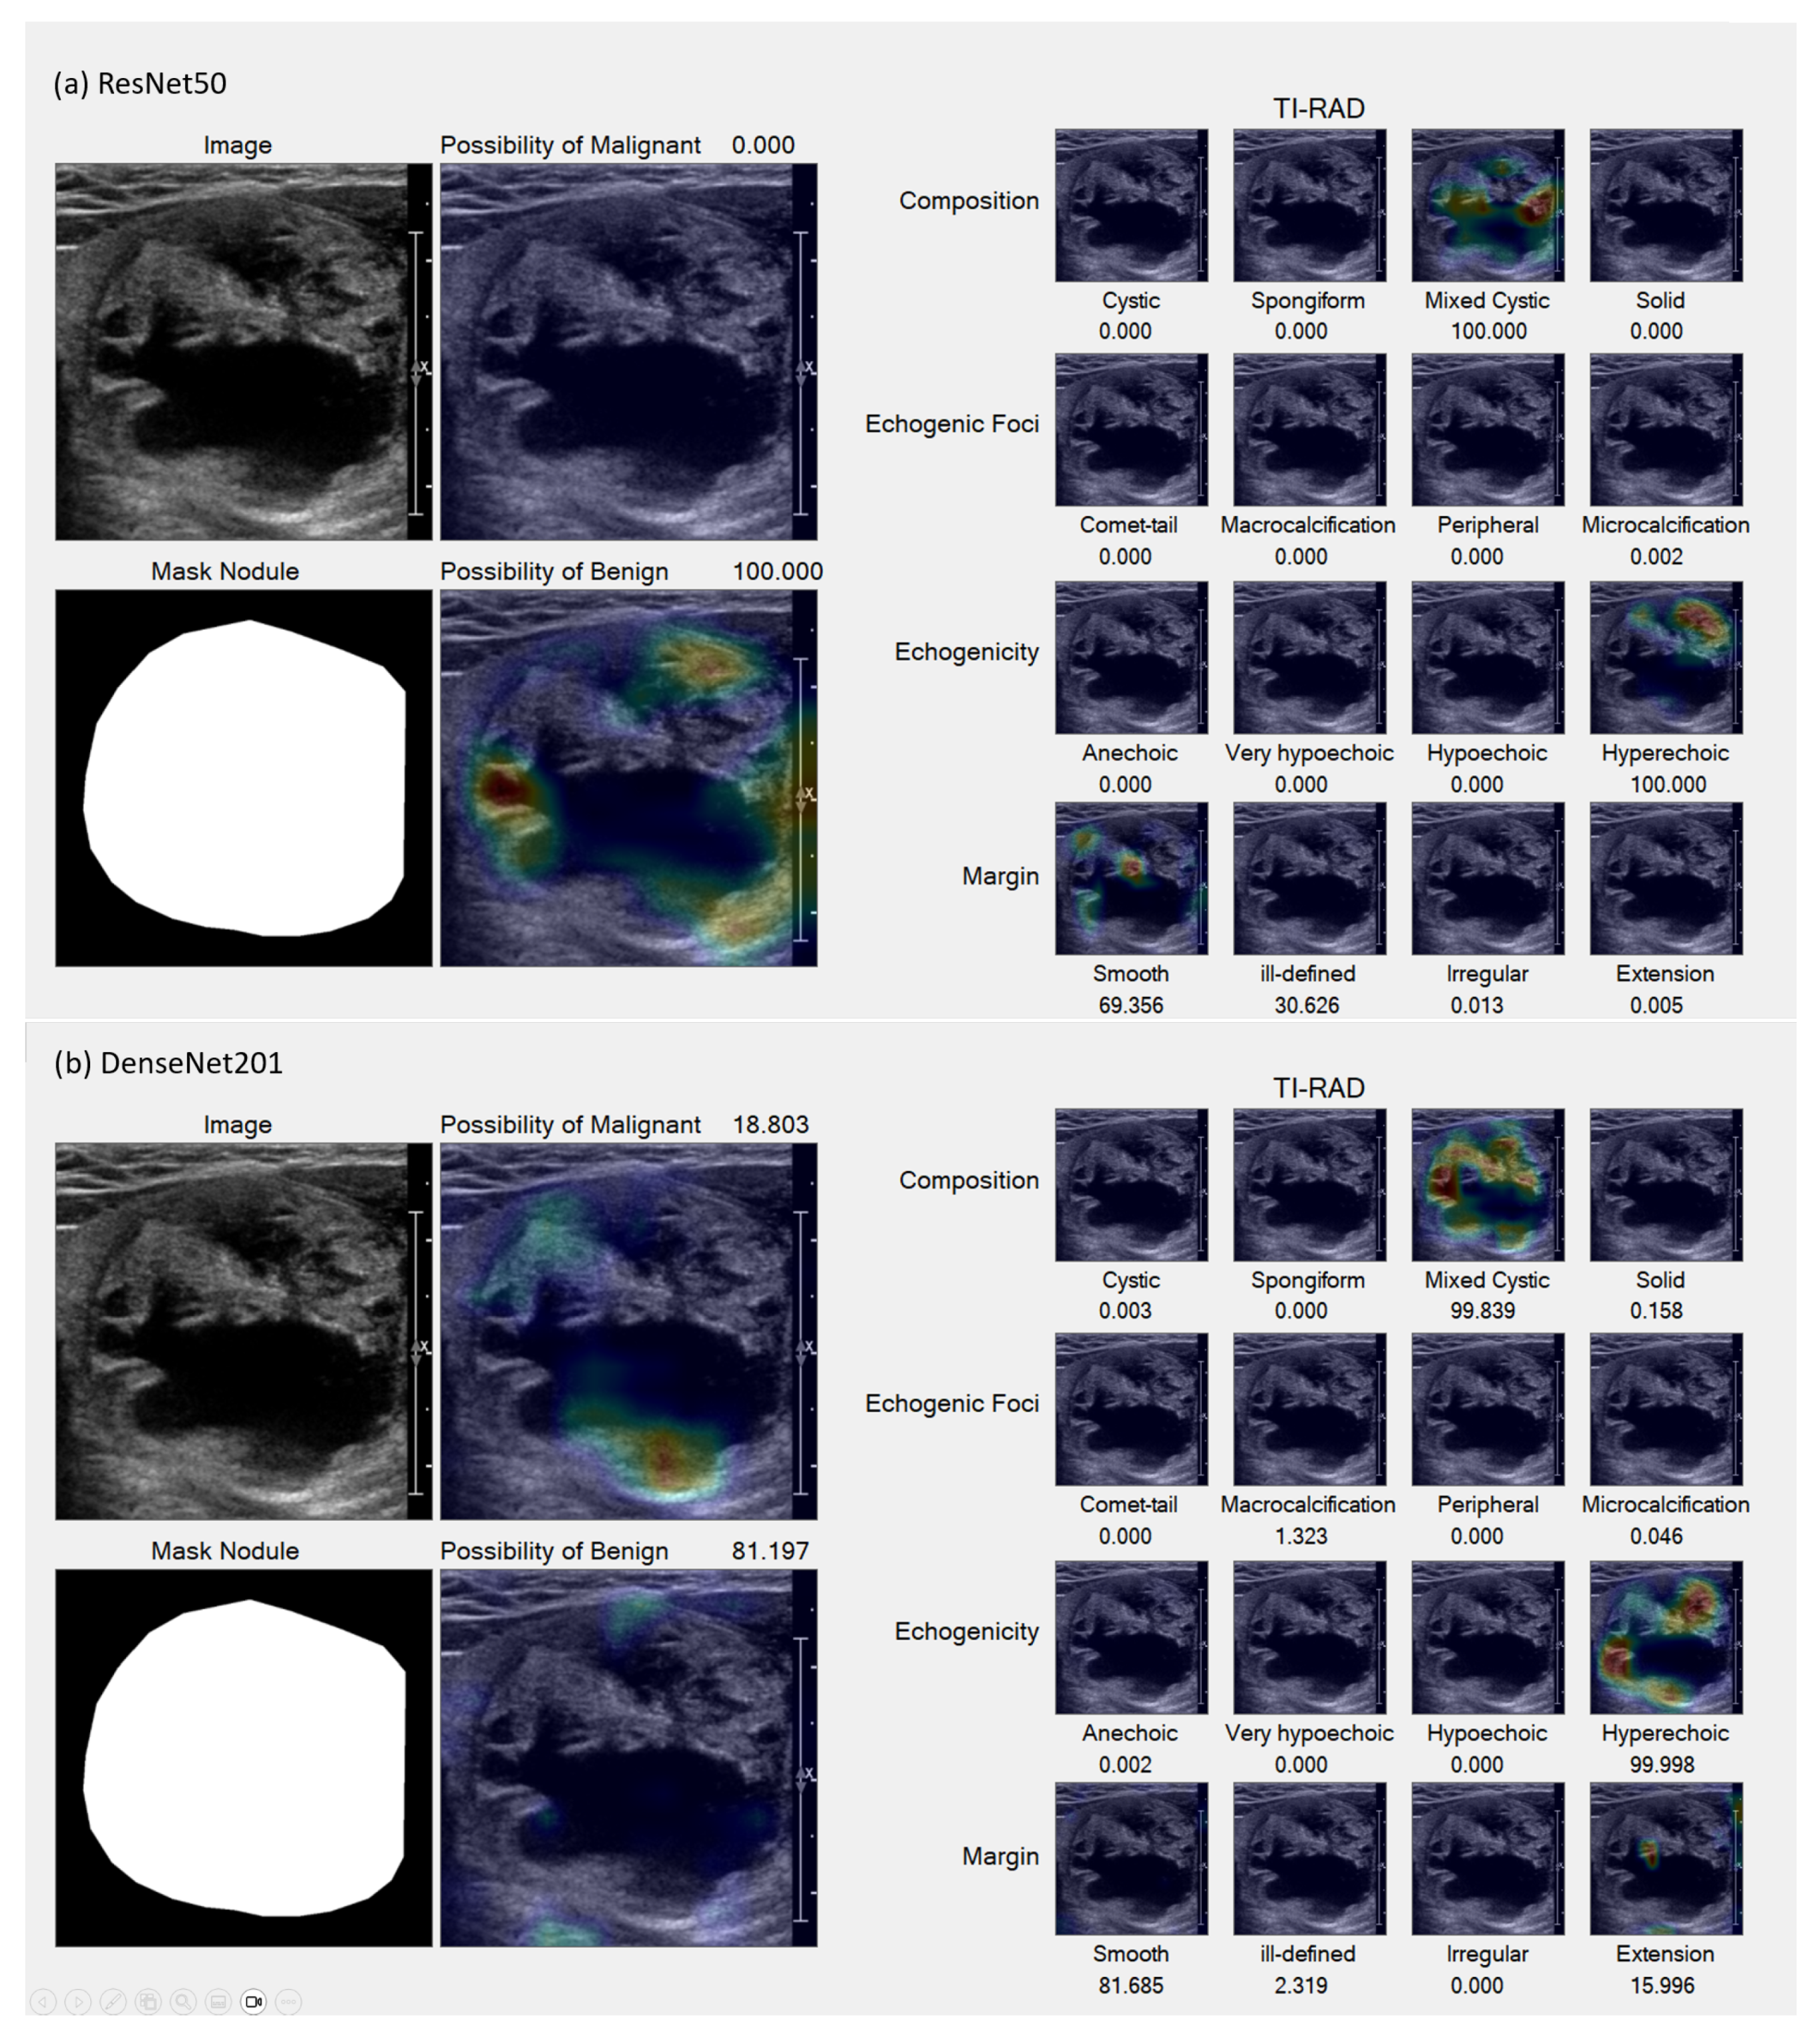

In the Grad-CAM visualization, we conducted individual analyses for each classification and sought the expertise of expert radiologists (coauthors DS and SB) to interpret the results.

Figure 7 and

Figure 8 present sample accurate outcomes along with corresponding expert explanations, while

Figure 9 displays a sample incorrect outcome and the experts’ interpretations for those cases.

This study seeks to investigate AI-driven analyses that simulate the cognitive process of radiologists, specifically evaluating discrepancies from the foundational principles outlined by the ACR TI-RADS guidelines. The Grad-CAM results underscore that the AI models’ analytical capabilities are largely congruent with the reasoning of radiologists. However, an exception was noted in the AI system’s inability to differentiate between micro-calcifications and macro-calcifications—distinctions typically made based on calcification size.

Figure 7.

Samples of accurate results. (a,b) Benign lesion exhibiting well-defined mixed solid–cystic composition, classified under TI-RADS-2, thereby denoting a low suspicion for malignancy (1.5%). Both ResNet50 (a) and DenseNet201 (b) models accurately identified mixed solid–cystic components, the hyperechoic solid region, and the smooth border, all of which contributed to a high likelihood of a benign diagnosis.

Figure 7.

Samples of accurate results. (a,b) Benign lesion exhibiting well-defined mixed solid–cystic composition, classified under TI-RADS-2, thereby denoting a low suspicion for malignancy (1.5%). Both ResNet50 (a) and DenseNet201 (b) models accurately identified mixed solid–cystic components, the hyperechoic solid region, and the smooth border, all of which contributed to a high likelihood of a benign diagnosis.